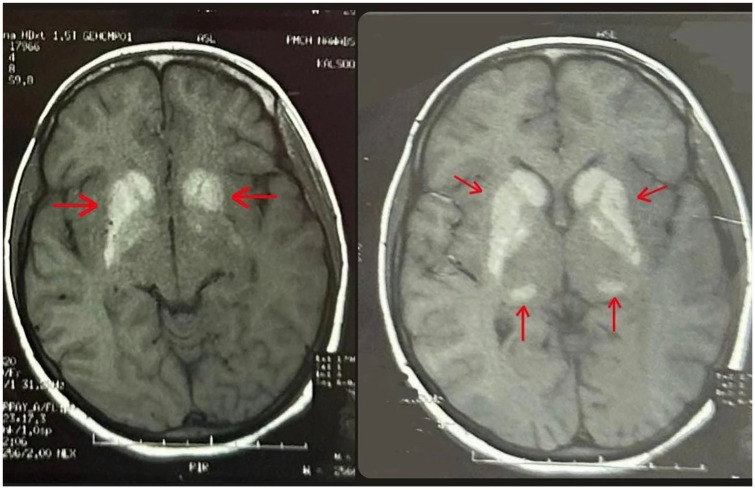

Fahr Syndrome or Strio-Pallido Dentate Calcinosis is a rare neurological syndrome characterized by deposition of calcium in basal ganglia, which usually occurs secondary to other underlying endocrinological disorders like hypo/hyper-parathyroidism. Symptoms vary greatly and may range from psychiatric ones like confusion and hallucination to neurological like Tremors, Rigidity, with seizures being the rarest manifestation. Laboratory tests and brain imaging play a crucial role in establishing the diagnosis, while treatment primarily focuses on managing symptoms. Here, we report a case of a 17-year-old female diagnosed with Fahr's syndrome secondary to hypo-parathyroidism, onset of the disease at such young age coupled with uncommon presentation of fits makes this case rather remarkable.

Abstract Image